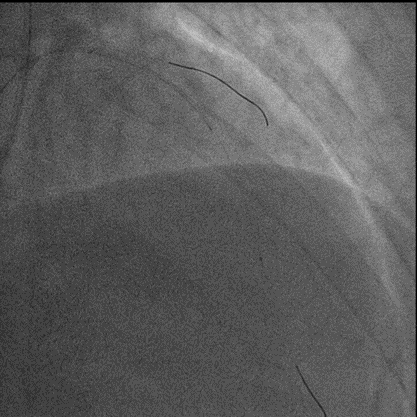

7F XB3.5,Cosair,Runthrough中间支保护,Pilot200正向进入D1,Pilot200 无法通过病变,交换Judo导丝

更换Judo3顺利到达LAD远端,Cosair跟进交换Runthrough